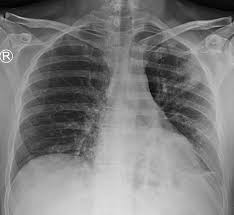

Air-space opacification is a descriptive term that refers to filling of the lung parenchyma with material that attenuates x-rays more than the unaffected surrounding lung tissue. Consolidation or ground-glass opacity occurs when alveolar air is replaced by fluid pus blood cells or other material. Test results for infl uenza virus respiratory fl uorescent antibodies D3 Ultra DFA Respiratory Virus Screening and In-fectious Disease Kit.

Air cant get through the consolidation so your lung cant do its job of bringing in fresh air and removing the air your body has used. The location retrocardiac - behind the heart shouldnt make a difference. Identifying multifocal air-space disease on CXR can be a significant clue to COVID-19 pneumonia.

Patchy diffuse air space consolidation. Diagnostic Hy-brids Inc Athens OH USA and virus culture were negative. There are a number of different causes of insult to the alveoli including build up of fluid hemorrhage infection malignancy and build up of protein and mineral deposits.

The location retrocardiac - behind the heart shouldnt make a difference. It is the radiological correlate of the pathological diagnosis of pulmonary consolidation. The most common clinical causes of this CT pattern of disease include hypersensitivity pneumonitis sarcoidosis atypical infections eg those caused by Mycoplasma pneumoniae with associated bronchiolitis and acute interstitial pneumonia 25. The particular way the lung collapses can often produce a. Acinar or air-space nodules. CT 5-mm slice thickness in a patient with bilateral consolidation. Tendency to coalesce near hila.